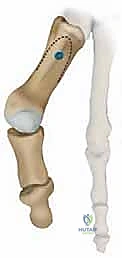

الخطوة 3: اختيار التقنية الجراحية العظمية المناسبة

بناءً على سبب الفشل الأولي، يختار الدكتور هطيف إحدى التقنيات التالية:

أ. إعادة القطع العظمي (Revision Osteotomy - Scarf or Chevron)

إذا كان الفشل ناتجًا عن تصحيح غير كافٍ في الجراحة الأولى، وكان المفصل لا يزال سليمًا (لا توجد خشونة شديدة)، يقوم الدكتور هطيف بإجراء قطع عظمي جديد (مثل تقنية Scarf أو Chevron) لإعادة توجيه العظم وتثبيته بمسامير تيتانيوم حديثة لا تسبب تهيجًا.

ب. عملية لابيدوس (Lapidus Procedure - TMTJ Arthrodesis)

إذا كان سبب التكرار هو "فرط الحركة" في مفصل منتصف القدم (TMTJ)، فإن الحل الوحيد لمنع التكرار المستقبلي هو دمج (إيثاق) هذا المفصل. يزيل الدكتور هطيف الغضروف من المفصل، يصحح زاوية العظم، ويثبته بشريحة معدنية قوية ومسامير حتى يلتحم العظمان معًا. هذه العملية تعالج أصل المشكلة من الجذور.

ج. إيثاق مفصل المشط السلامي الأول (First MTPJ Arthrodesis)

يُعتبر هذا الإجراء "المعيار الذهبي" (Gold Standard) وجراحة الإنقاذ النهائية في حالات المراجعة المعقدة، خاصة إذا كان المريض يعاني من:

* تدمير المفصل أو خشونة شديدة (التهاب المفاصل العظمي).

* فقدان عظمي كبير من الجراحة السابقة.

* تكرار شديد للتشوه مصحوب بألم مبرح.

في هذه العملية، يتم إزالة الغضروف التالف من مفصل الإصبع الكبير، ودمج العظام معًا في وضع مستقيم قليلاً للأعلى للسماح بالمشي الطبيعي. يتم التثبيت باستخدام شريحة ومسامير متقاطعة. النتيجة هي إصبع مستقيم، خالٍ تمامًا من الألم، ولا يمكن أن يعود للتشوه أبدًا.